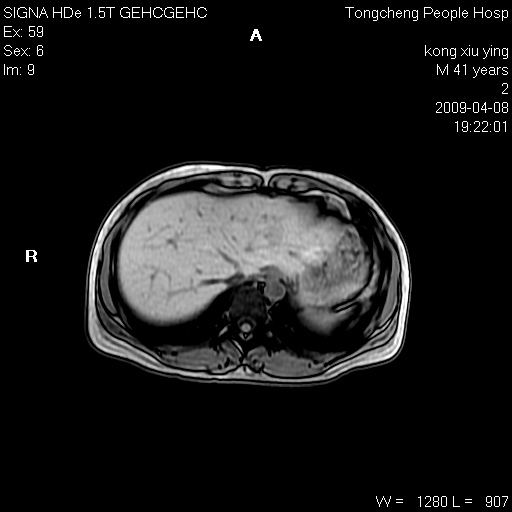

标题: CL1008:【经典】胆囊石榴籽样结石。

女,41岁。健康体检——彩超提示:胆囊显示不清。平素健康,无不适感。

腹部mr扫描及mrcp,图像如下:

胆囊石榴籽样结石。